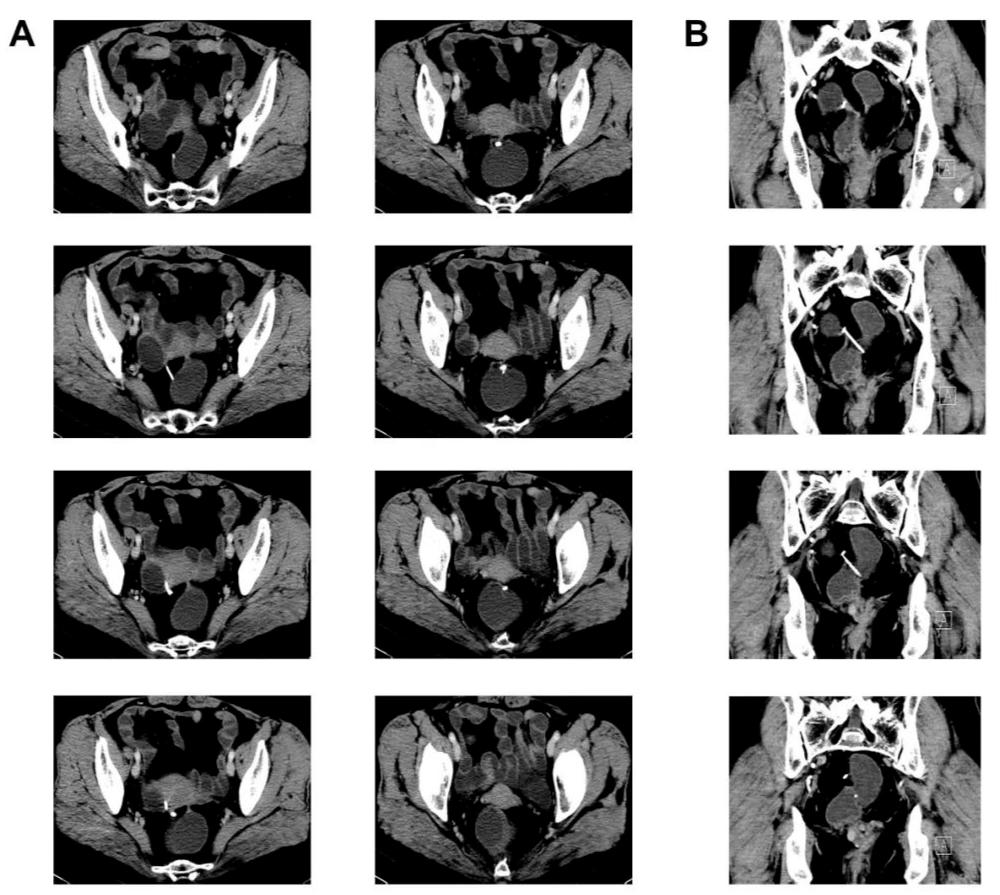

3.术前辅助检查

图1

图2